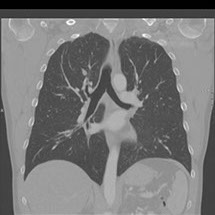

Le scanner comporte un lit d'examen, sur lequel le patient est allongé, qui va se déplacer lentement pendant l’examen et un anneau qui va tourner autour du patient en émettant des rayons X (il contient le tube à rayons X et les récepteurs). Les rayons X vont traverser la région à étudier et permettre d’obtenir des images en coupe de la zone à étudier. Des traitements de numérisation informatique permettront d'obtenir  des images 2D ou 3D dans différents plans et volumes.

• Les pathologies thoraciques (infection, tumeurs …).